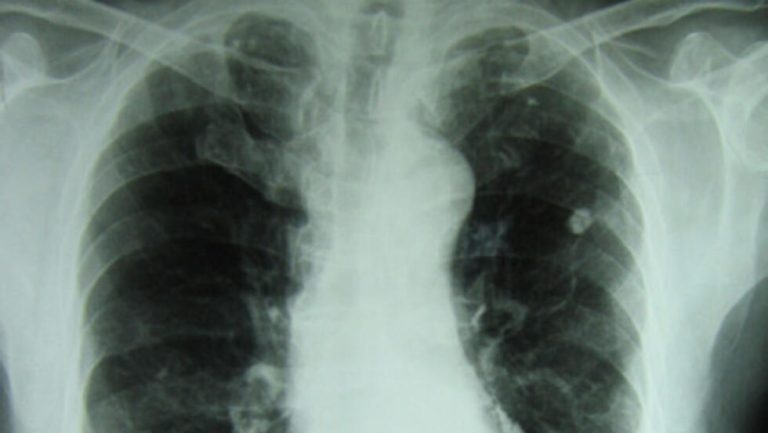

Cerca de 125 mil pessoas vivem com a tuberculose, no País. A maioria dos casos concentra-se nas províncias do sul.

São dados apresentados, à Rádio Moçambique, pela Chefe do Programa Nacional de Controle da Tuberculose, Benedita José, no quadro da passagem, hoje, do dia mundial de luta contra a doença.

Moçambique é actualmente o quarto país com mais casos da tuberculose, na África Austral. (RM)